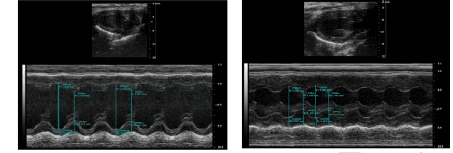

模型验证:术后8周进行心脏超声检测:结果表明与对照组相比,模型组左心室在舒张期或收缩期的直径明显缩小。